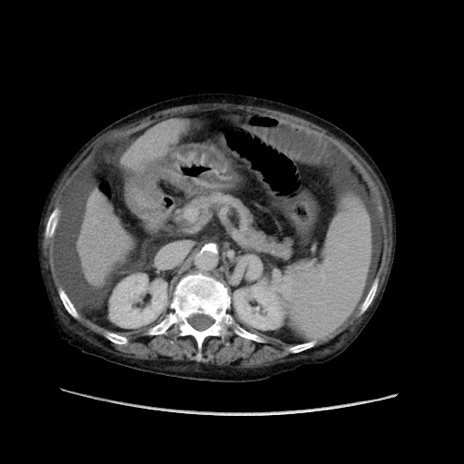

症例31(横断像)

【症例】80歳代 女性

【主訴】腹部膨満感

【現病歴】他院にて肝硬変にてフォロー中。1週間前から便秘、腹部膨満感、臍部腫瘤あり受診となる。

【既往歴】肝硬変

【身体所見】腹部膨隆あり、皮膚変化なし、疼痛なし。

【データ】WBC 4600、CRP 0.25